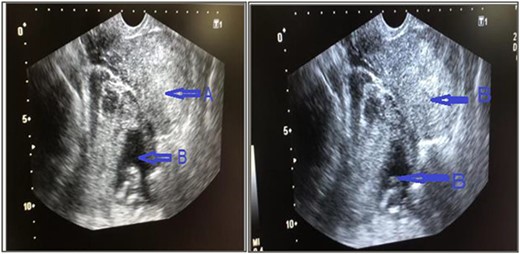

Urgent trans vaginal ultrasound was done which revealed empty uterine cavity, live fetus corresponding to 14 weeks 6 days on the left adnexa and moderate amount of free fluid in the Douglas Cul-de-sac (Fig. 1). The placenta was on the posterior aspect but its full margins were not well visualized. Impression was live intra-abdominal ectopic pregnancy at GA 14 weeks and 6 days. Her hemoglobin was 9.4 g/dl and urgent requisition for two blood units was sent. Basic laboratory parameters, including blood glucose, liver enzymes, renal function tests, and electrolytes were within normal limits The patient was taken up for emergency laparotomy after taking written and informed consent from the patient and her relative.

Trans vaginal ultrasound was done that showed, (a) empty uterine cavity, with no gestational sac, (b) live fetus of 14 weeks 6 days in left adnexa and moderate amount of free fluid in pelvis.